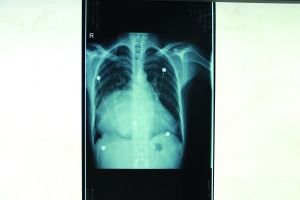

X光片显示巨大心脏填满了整个胸腔 院方供图

在X光片结果出来后,南京市第一医院心胸外科副主任医师徐明感到段先生的病情非同一般,病人的心脏几乎填满了整个胸腔——正常人的心脏宽度只占到胸腔空间的二分之一,而段先生的心脏占据了95%的空间。普通人左心房直径只有40毫米左右,而病人达到124毫米,整个心脏如排球那么大,是正常人的8倍。肺部和支气管受到严重压迫,靠着仅存的一点点肺,勉强呼吸。